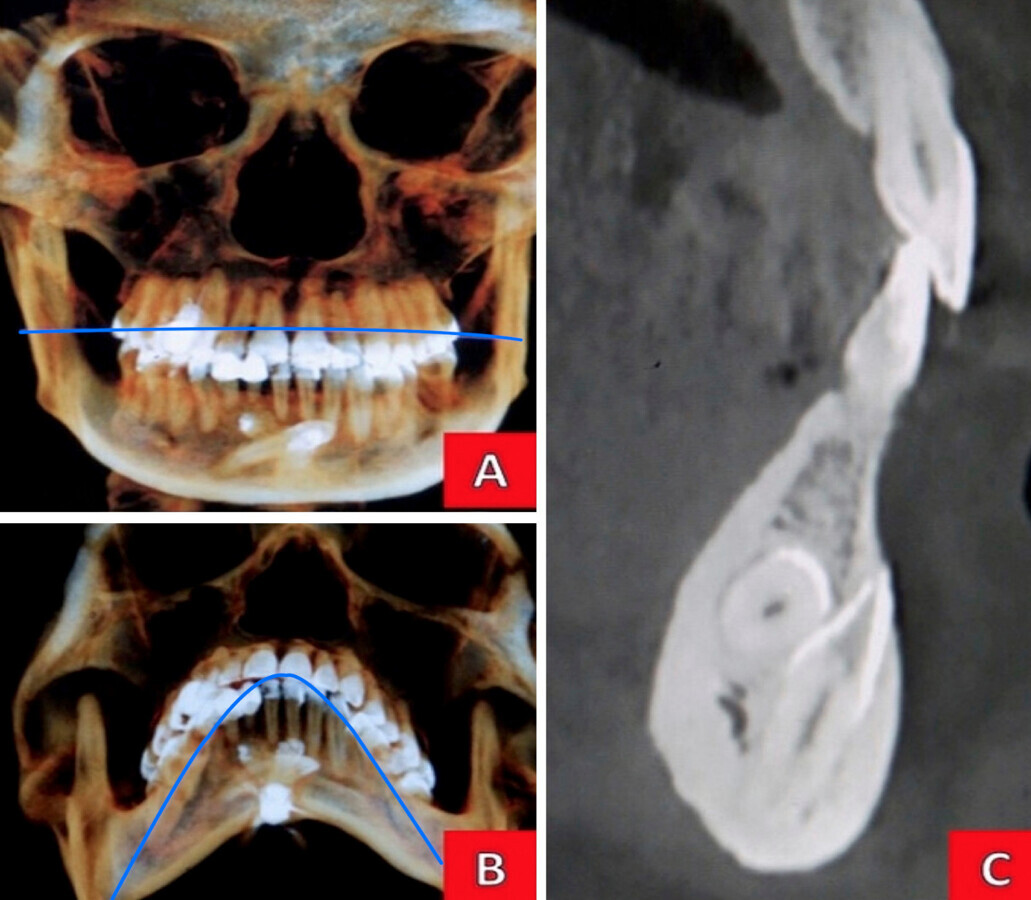

Figura 2. A) Imagen de diente supernumerarios rudimentarios observados en TAC (Ejemplar 1, orientación vertical, hacia distal; Ejemplar 2: posición transversa, distoposterior). B) Imagen coronal de mandíbula vista inferior. C) Imagen de contraste en escala de grises del mentón, corte sagital.

Se presentó un paciente de 37 años, sexo femenino. El motivo de la consulta referido es: “Ligero dolor e inflamación en la encía por un golpe en el diente hace seis meses”. No refiere ningún síndrome, enfermedad o patología sistémica, ni medicación actual; es una paciente que responde con actitud colaboradora. En el examen clínico intraoral se observa una dentición permanente con tejidos blandos normales, restauraciones metálicas y estéticas sin desajuste. Falta de cordales (refiriendo esta ausencia por extracción previa a tratamiento ortodóntico, finalizado cuatro años antes). A la exploración, el diente 22 presenta una restauración mesio-palatina con composite y fractura del esmalte en el tercio incisal distal de la corona y fracturas verticales perceptibles al método de transiluminación. En el fondo del saco la paciente refiere ligero malestar a la digito-palpación. Se tomo una radiografía periapical inicial en la que se observa radiolucidez difusa y no definida en el periápice (Figura 1). Para una minuciosa observación adicional y como soporte de la planeación endo-quirúrgica, se solicitó un TAC, observando en la cita subsecuente mediante contrastes específicos la zona perirradicular, apreciando el alcance de la lesión y las estructuras involucradas (Figura 1). En la revisión de este mismo estudio, en el cuerpo mandibular también se localizaron dos dientes supernumerarios; ubicados en la línea media, uno en posición transversa, distoposterior, y el otro en orientación vertical, hacia distal, comprometiendo el conjunto de dientes anteriores inferiores. (Figura 2)